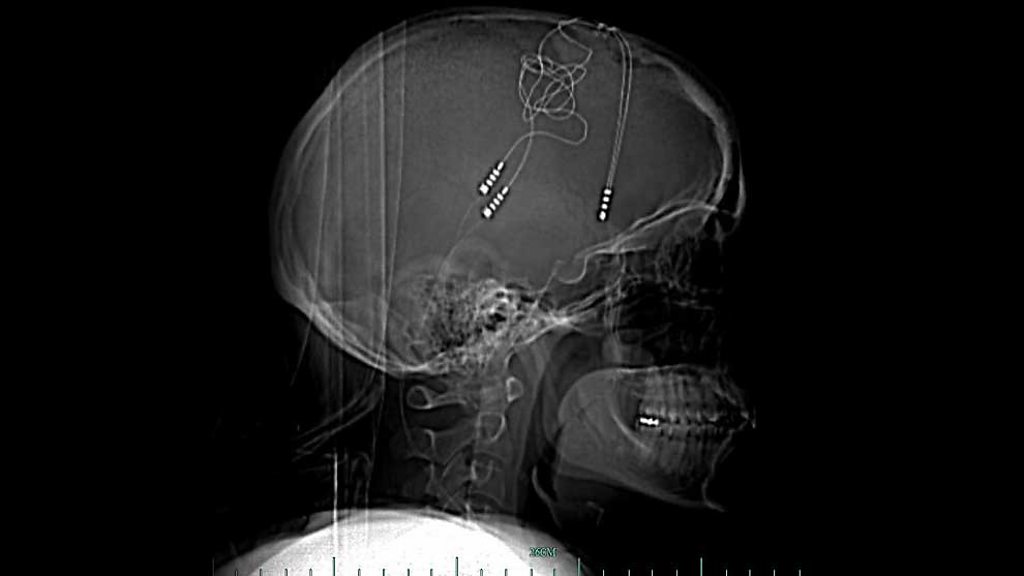

When all the other treatments failed to help her depression Brandy Ellis turned to technology. She now has electronics in her brain to regulate her emotions. She explains whether she feels more or less human as a result.